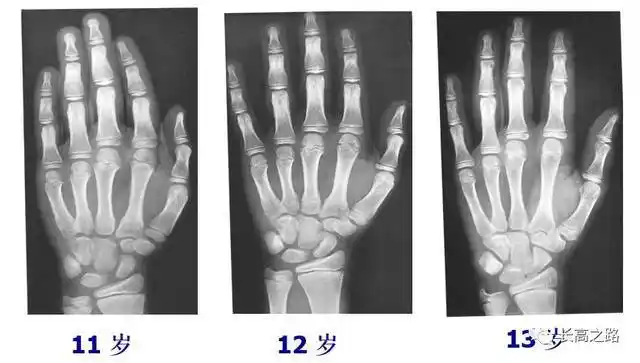

教你简单识别孩子的骨龄片

12岁的孩子出现这样的骨龄(14岁),孩子身高目前只有148cm,预计成年

中国儿童标准骨龄片

收藏丨骨龄图谱方便随时对照